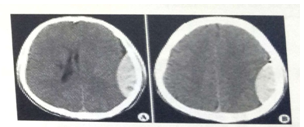

試題2:男,44歲。頭部外傷12小時(shí)。結(jié)合CT片,此診斷為(2分)

A.硬膜下血腫

B.腦出血

C.硬膜外血腫

D.顱骨骨折

E.腦血栓

答案:C